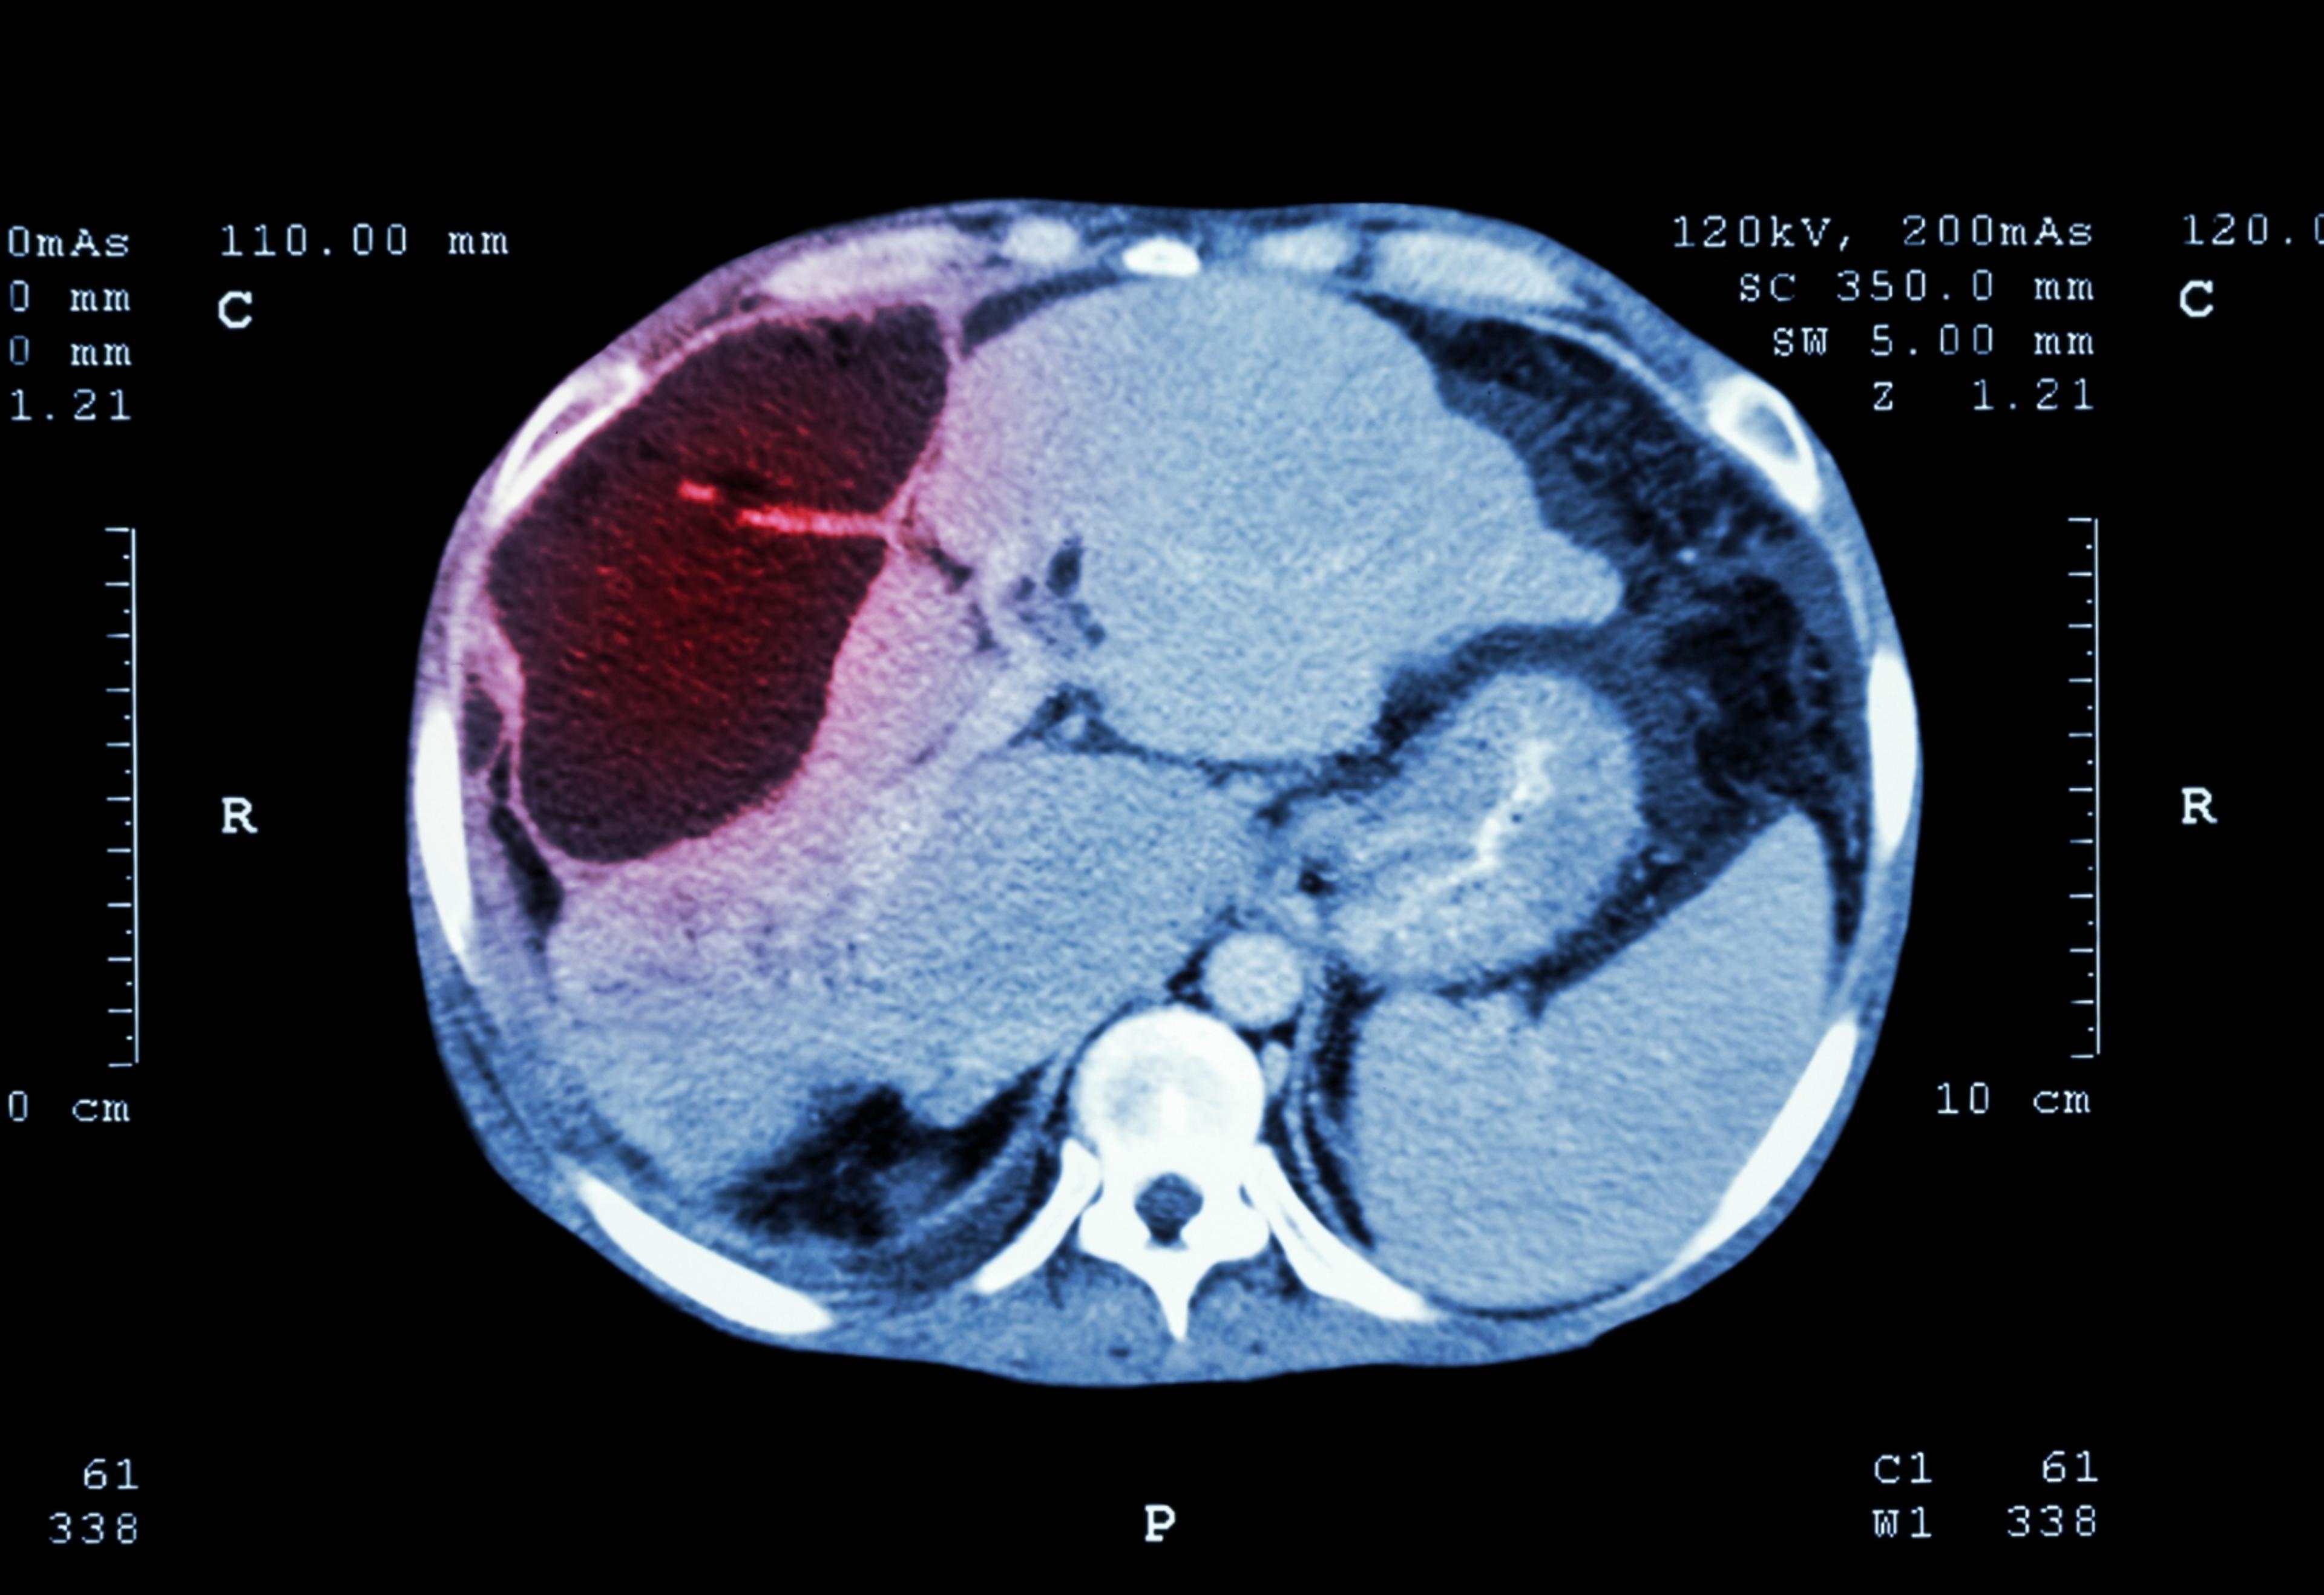

- Yttrium 90 Radioembolization for Liver Cancer

This treatment selectively targets liver tumors to improve survival and quality of life. Yttrium-90 radioembolization is performed as an outpatient procedure and is very well tolerated.